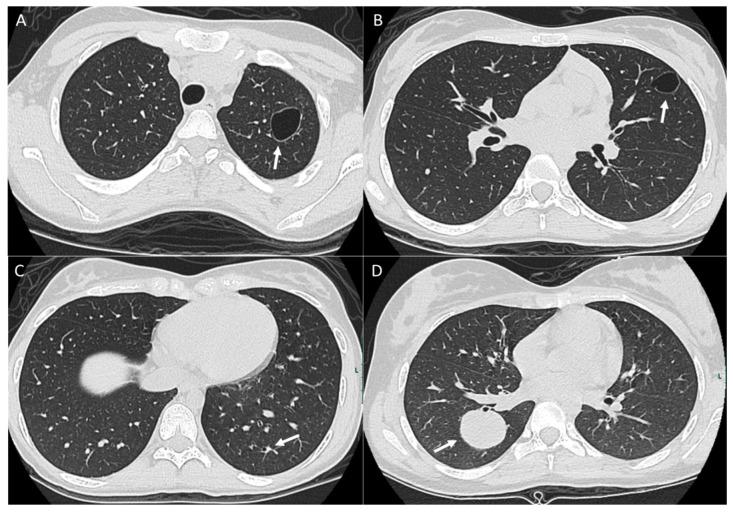

Osteosarcoma, a primary bone malignancy in children and adolescents, frequently metastasizes to the lungs, contributing significantly to morbidity and mortality. At diagnosis, 15-20% of patients present with detectable lung metastases. Chest computed tomography (CT) is vital for the early detection and monitoring of these metastases. Lung involvement typically presents as multiple nodules of varying sizes and can include atypical features such as cavitation, cystic lesions, ground-glass halos, intravascular tumor thrombi, and endobronchial disease. Pleural metastasis often occurs alongside pulmonary disease, and complications like spontaneous pneumothorax may arise. Additional findings may include thoracic lymphadenopathy, cardiac tumor thrombus, and chest wall deposits. Familiarity with these imaging patterns is essential for radiologists to ensure timely diagnosis and effective management. This review highlights the critical role of chest CT in detecting and characterizing osteosarcoma metastasis.

骨肉瘤是儿童和青少年常见的原发性骨恶性肿瘤,常转移至肺部,对发病率和死亡率有显著影响。在诊断时,15%至20%的患者出现可检测到的肺转移。胸部计算机断层扫描(CT)对于这些转移灶的早期检测和监测至关重要。肺部受累通常表现为大小不一的多个结节,可包括一些非典型特征,如空洞形成、囊性病变、磨玻璃晕、血管内肿瘤血栓和支气管内病变。胸膜转移常与肺部疾病同时发生,可能出现自发性气胸等并发症。其他表现可能包括胸内淋巴结肿大、心脏肿瘤血栓和胸壁转移灶。放射科医生熟悉这些影像学表现对于确保及时诊断和有效治疗至关重要。本综述强调了胸部CT在检测和鉴别骨肉瘤转移方面的关键作用。